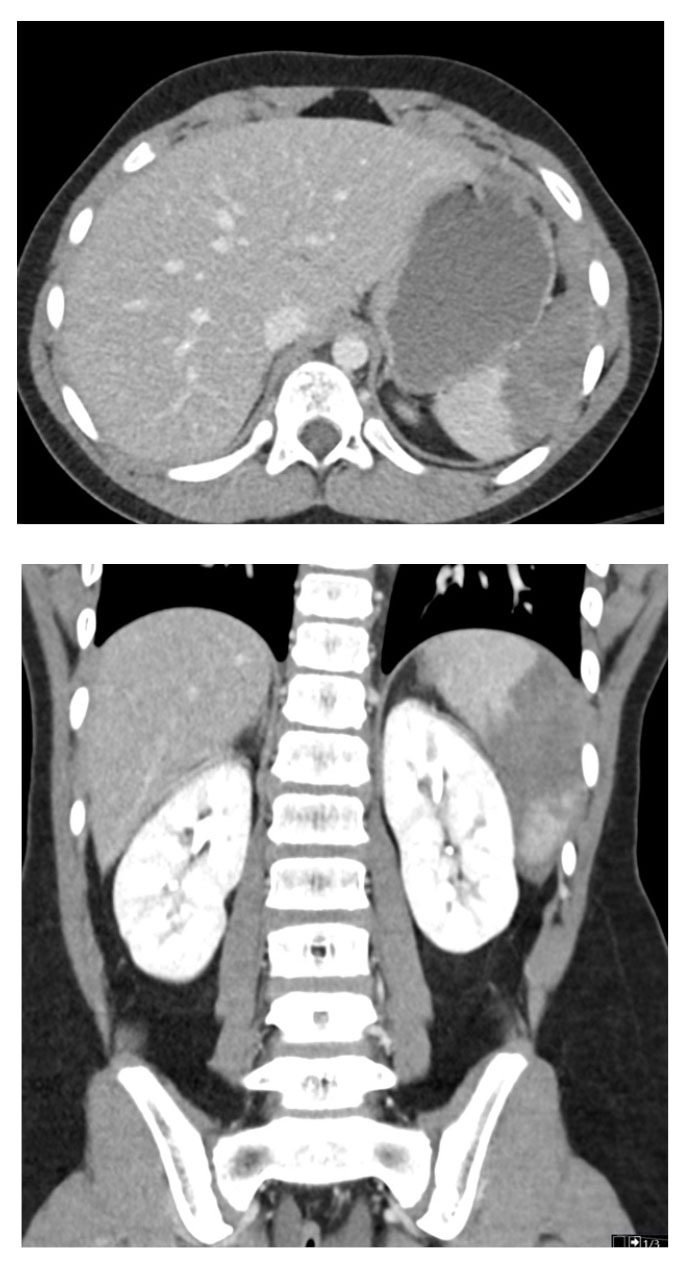

Additional studies have further noted that the PECARN prediction rule, when combined with clinical suspicion, limited the number of CT scans without significant negative consequences.46 Streck et al developed a tool to assess risk and the need for CT scans. The Streck prediction rule includes laboratory results in addition to an abnormal exam and history of abdominal pain. The rule has a negative predictive value of more than 99% in identifying patients without serious intraabdominal injury.47 It has been shown that the implementation of a protocol using such decision tools can significantly decrease the number of abdominal CT scans performed, without increasing the rate of missed injuries.48-50 For an example of a splenic injury, see Figure 4.

Figure 4. Splenic Laceration |

Axial and coronal images from computed tomography with intravenous contrast show a splenic laceration with more than 25% of the spleen showing non-enhancement compatible with devascularization, American Association for Surgery of Trauma (AAST) grade 4. Source: Courtesy of Mark Warren, DO, Dayton Children’s Hospital, Department of Radiology |